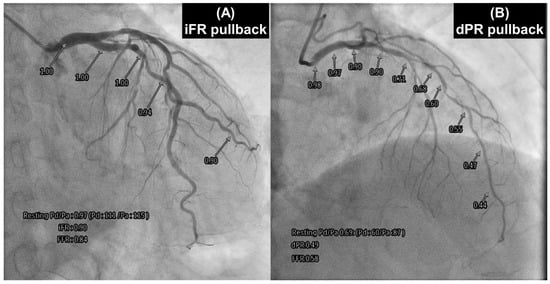

3.4. NHPR Pullback

- Warisawa, T.; Cook, C.M.; Howard, J.P.; Ahmad, Y.; Doi, S.; Nakayama, M.; Goto, S.; Yakuta, Y.; Karube, K.; Shun-Shin, M.J.; et al. Physiological pattern of disease assessed by pressure-wire pullback has an influence on fractional flow reserve/instantaneous wave-free ratio discordance. Circ. Cardiovasc. Interv. 2019, 12, e007494. [Google Scholar] [CrossRef] [PubMed]

- Omori, H.; Kawase, Y.; Mizukami, T.; Tanigaki, T.; Hirata, T.; Kikuchi, J.; Ota, H.; Sobue, Y.; Miyake, T.; Kawamura, I.; et al. Comparisons of nonhyperemic pressure ratios: Predicting functional results of coronary revascularization using longitudinal vessel interrogation. JACC Cardiovasc. Interv. 2020, 13, 2688–2698. [Google Scholar] [CrossRef]

- Kikuta, Y.; Cook, C.M.; Sharp, A.S.P.; Salinas, P.; Kawase, Y.; Shiono, Y.; Giavarini, A.; Nakayama, M.; De Rosa, S.; Sen, S.; et al. Pre-angioplasty instantaneous wave-free ratio pullback predicts hemodynamic outcome in humans with coronary artery disease: Primary results of the international multicenter iFR GRADIENT registry. JACC Cardiovasc. Interv. 2018, 11, 757–767. [Google Scholar] [CrossRef] [PubMed]